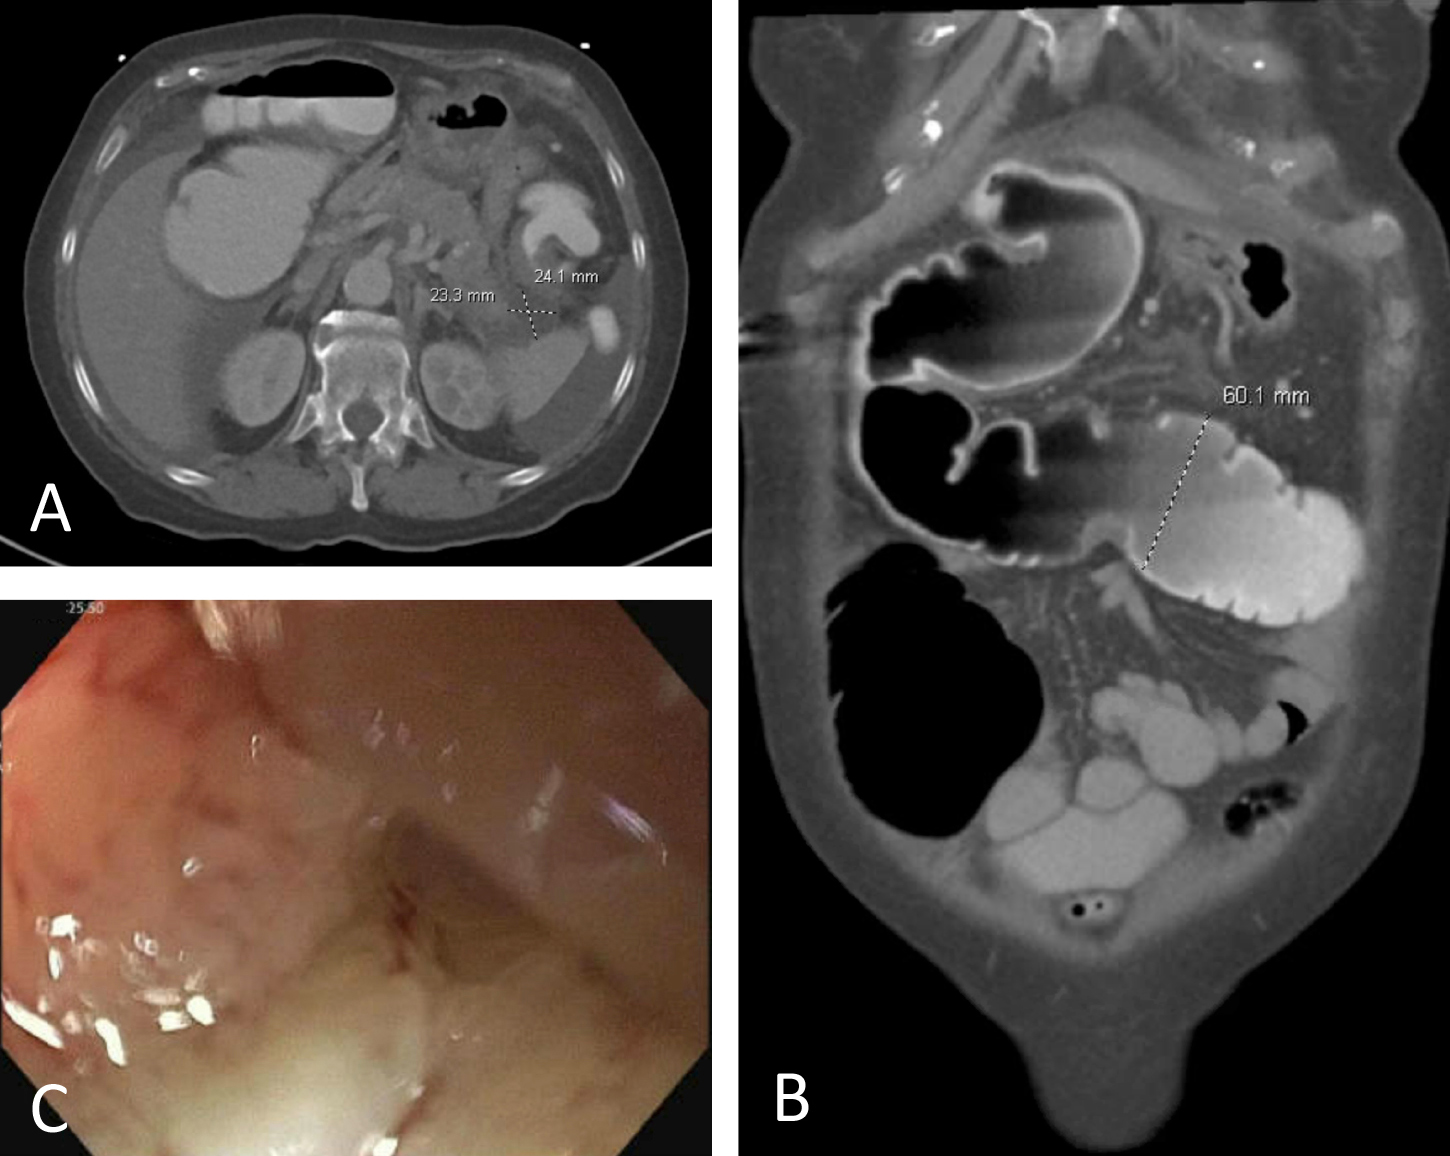

CT (A) axial view showing the pancreatic pseudocyst and (B) coronal view showing a dilated cecum and transverse colon. (C) Flexible sigmoidoscopy revealing a malignant-appearing tumor in the rectosigmoid colon, biopsied.